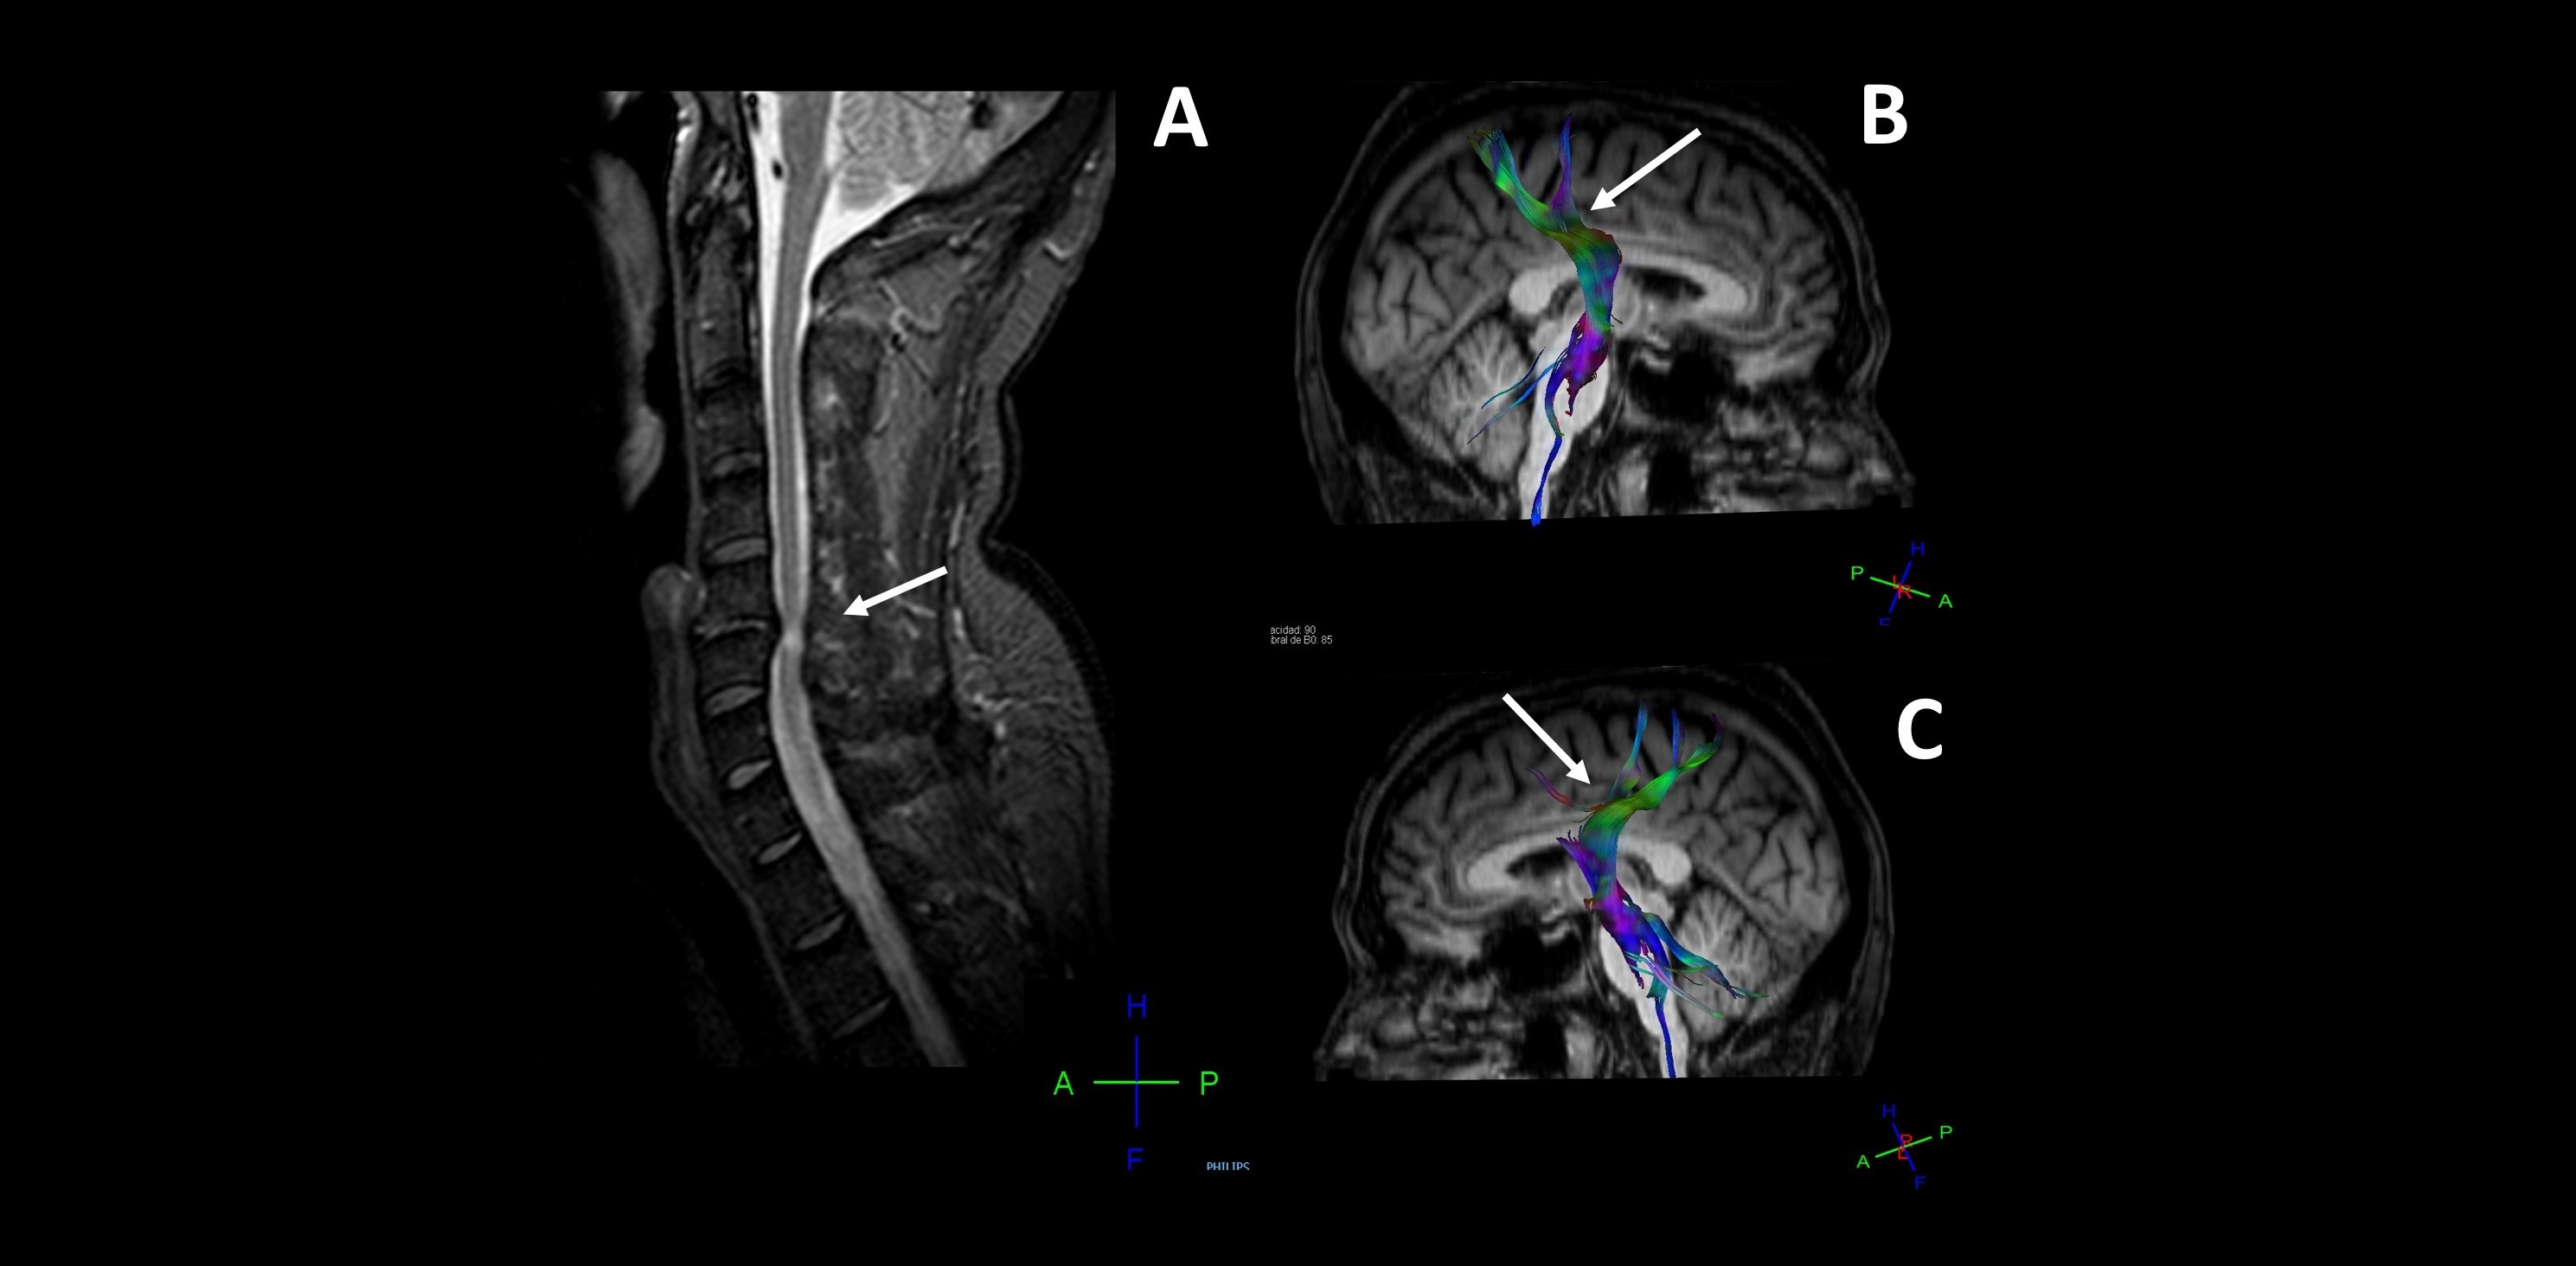

Los investigadores han aplicado herramientas y técnicas de neuroimagen médica avanzadas para tratar de entender mejor lo que sucede en el cerebro de pacientes crónicos con lesiones compresivas por hernias cervicales. Estas técnicas han permitido estudiar tanto la corteza cerebral como las fibras nerviosas de sustancia blanca y los patrones de conexión entre las distintas áreas cerebrales, lo que permite detectar cambios patológicos no observables en los estudios de resonancia magnética convencionales.

“Hemos demostrado que existen cambios a nivel cerebral y en las vías de comunicación de las señales cerebrales que se manifiestan sobre todo por atrofia cortical y daños en la corteza sensorial y motora” explica Eduardo Fernández Jover, coautor de la publicación y director del Grupo de Neuroingeniería Biomédica de la UMH y del CIBER-BBN. “Estos cambios se desconocían hasta ahora y pueden ayudar a comprender mejor la evolución clínica de muchos pacientes y abrir nuevas vías de diagnóstico y tratamiento de esta patología tan frecuente” añade.